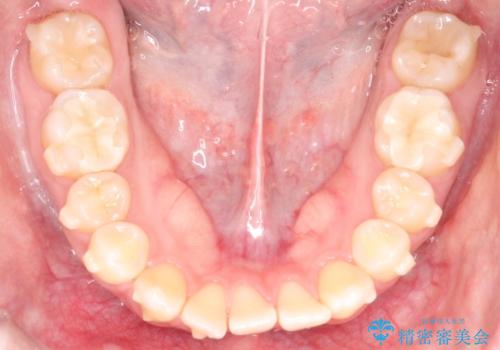

【インビザライン】歯を抜かずにできるだけ前歯を下げたい

- 前歯の前突を主訴に来院されました。

インビザライン を用いて、歯並びの改善を行うことができました。